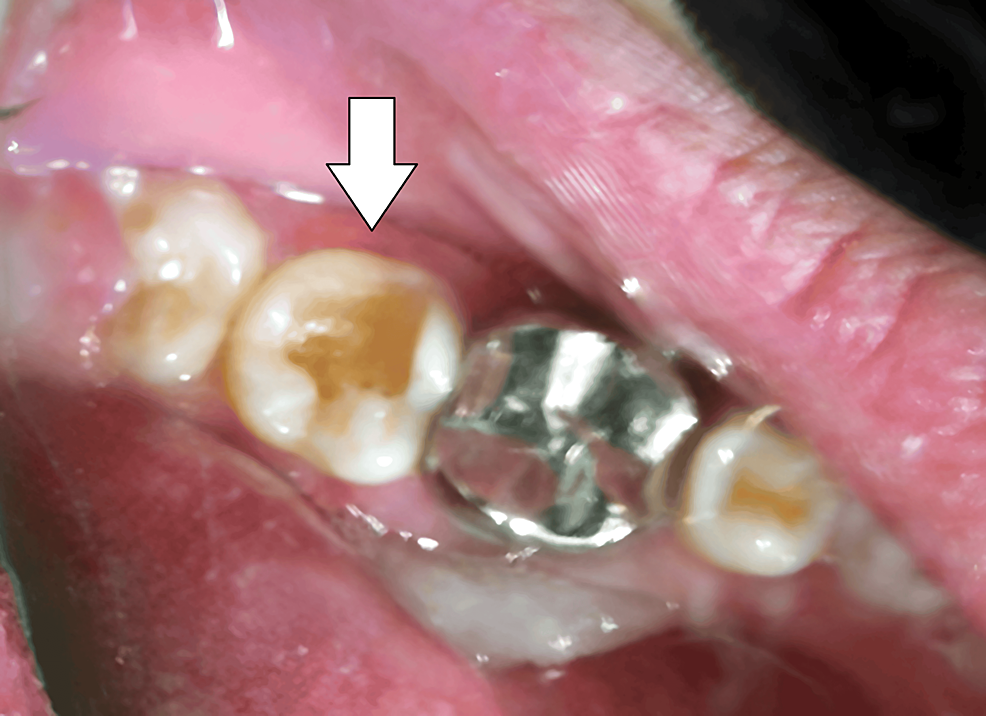

From www.cureus.com

PinRetained Amalgam An Intricate Restorative Case Study Cureus Pin Retained Amalgam the authors compared the clinical performance of complex amalgam restorations, replacing at. a pin retained restoration is an intricate restoration involving the insertion of one or more pins into the dentin to provide. a pin retained amalgam restoration may be defined as a type of complex amalgam restoration requiring the placement of one. — a pin. Pin Retained Amalgam.